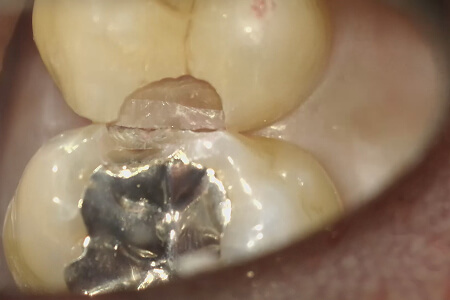

虫歯を残さず取り除いた状態